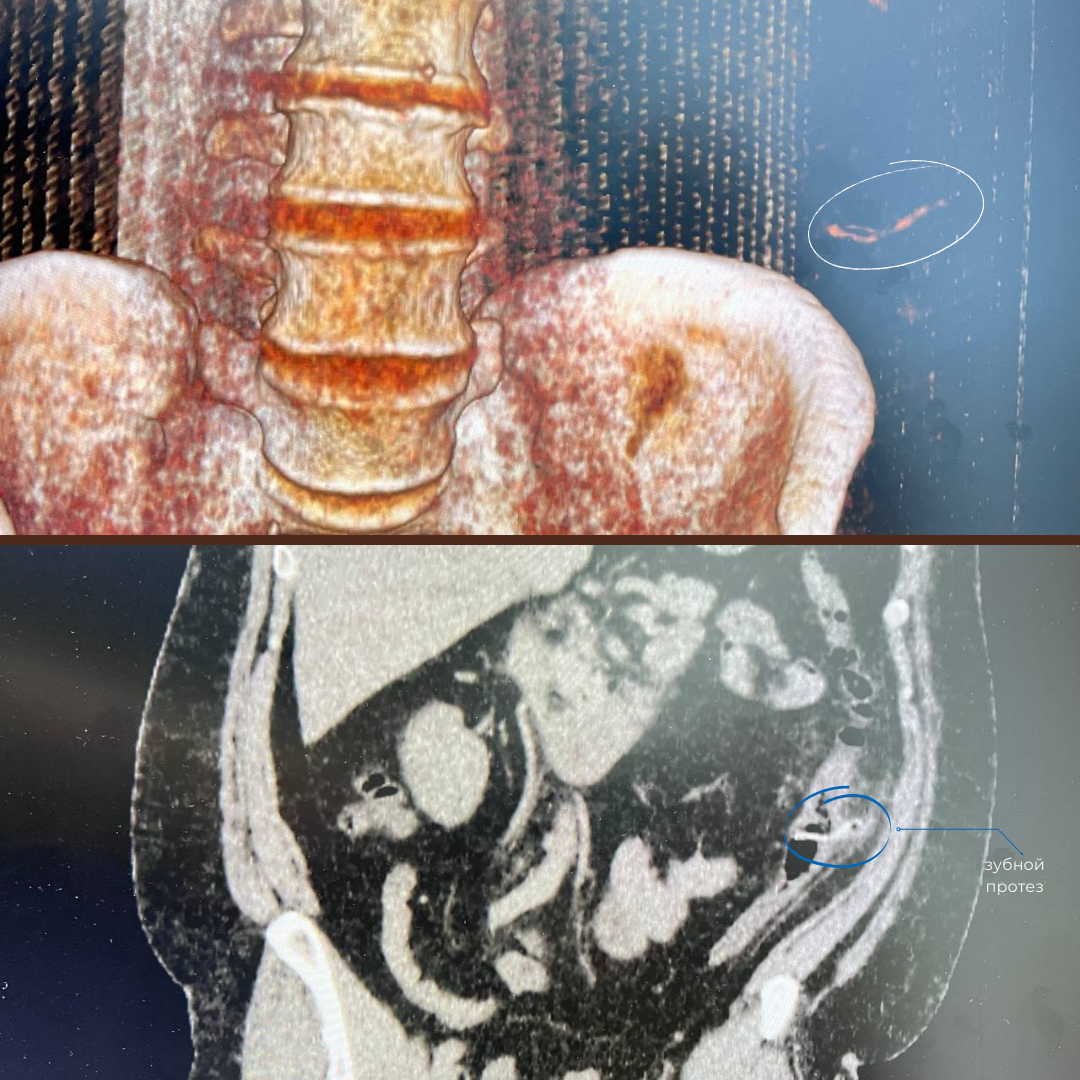

Мужчину срочно госпитализировали и провели компьютерную томографию. Результаты показали, что инородное тело находится в нисходящем отделе ободочной кишки и зацепилось за стенку кишечника, тем самым вызвав воспаление в этой области

Ахмад Джабборов, врач-эндокопист: «Сначала мы исключили возможную перфорацию кишечника, а затем приступили к операции: завели колоноскоп, осмотрели нужный участок кишки, «дошли» до зубного протеза, накинули на него эндоскопическую петлю и осторожно извлекли. Несмотря на то, что инородное тело находилось достаточно далеко, у нас получилось достать его, не усугубляя состояние пациента».